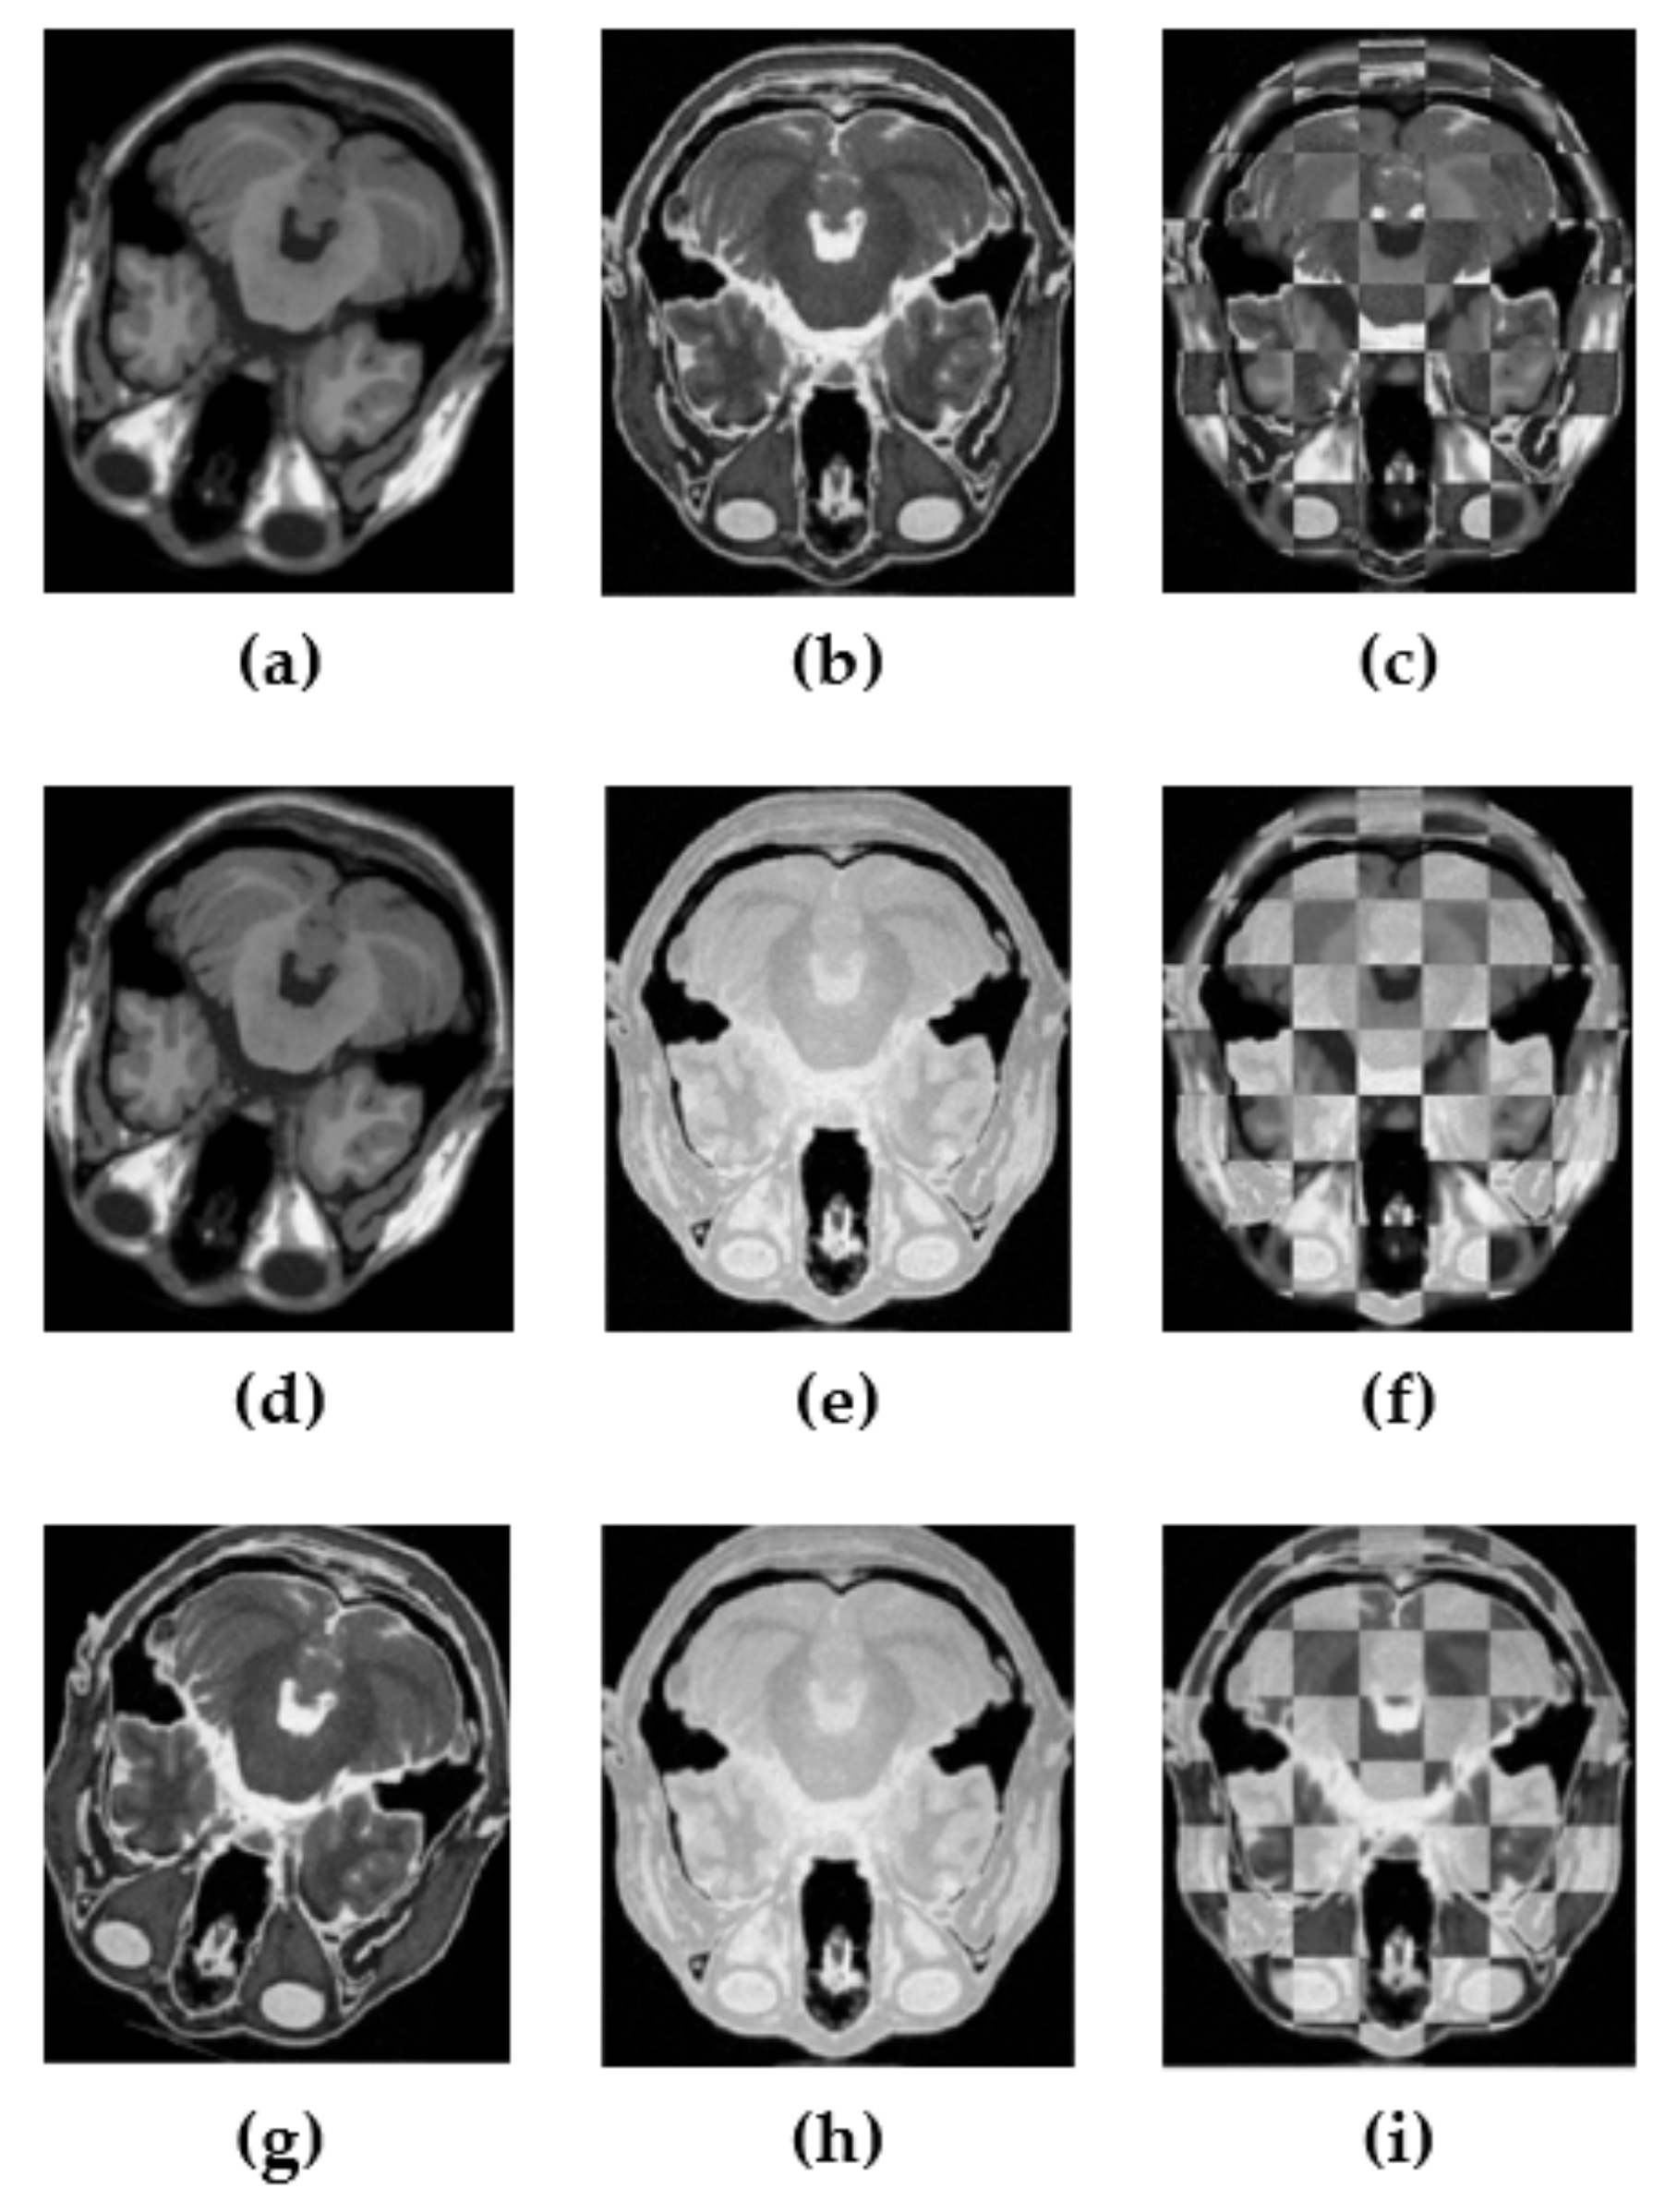

3. Experimental Results and Discussion